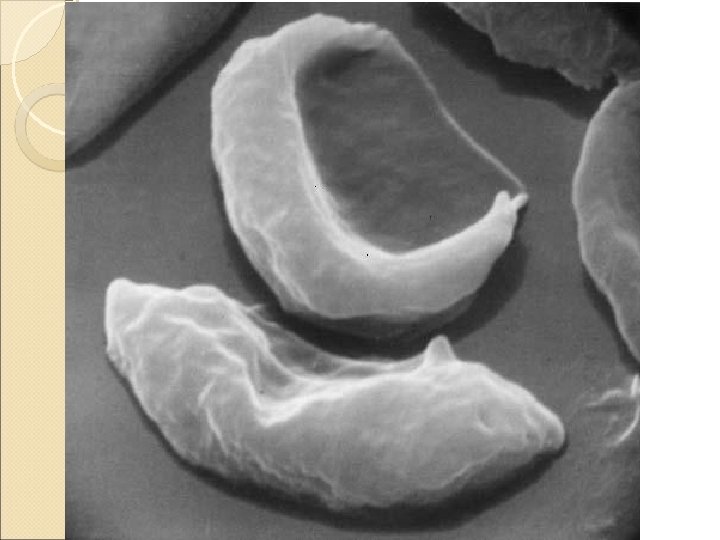

Sickle cell anemia �Qualitative hemoglobinopathy �Valine is substituted instead of glutamine in the sixth position on the globin molecule �Sickle cell anemia is caused by homozygosity for the sickle cell gene and is the most common form of sickle cell disease �The charge at this site is altered and allows for polymerization of Hb under conditions of hypoxia

Sickle cell anemia �Polymerization of sickle Hb ◦ distorts erythrocyte morphology ◦ causing a marked reduction in RBC life span ◦ increases blood viscosity ◦ predisposes to episodes of vasoocclusion

Sickle cell anemia-laboratory findings �Decreased Hb (7 -10 g/dl) with normal MCV �Reticulocytosis �Characteristic sickle cells �Hb electrophoresis ◦ Hb. S